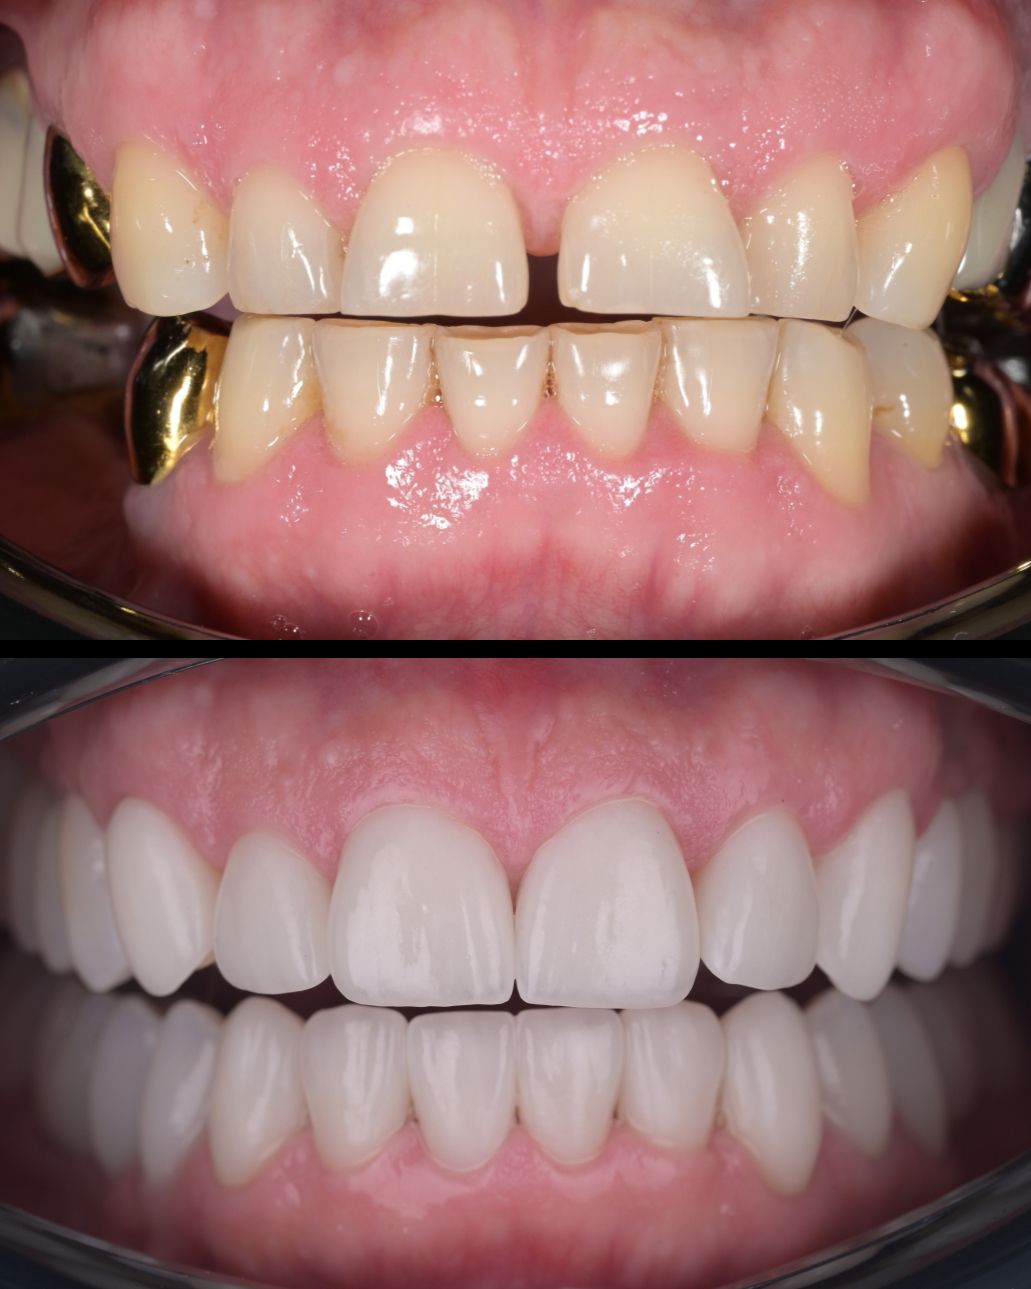

до и после